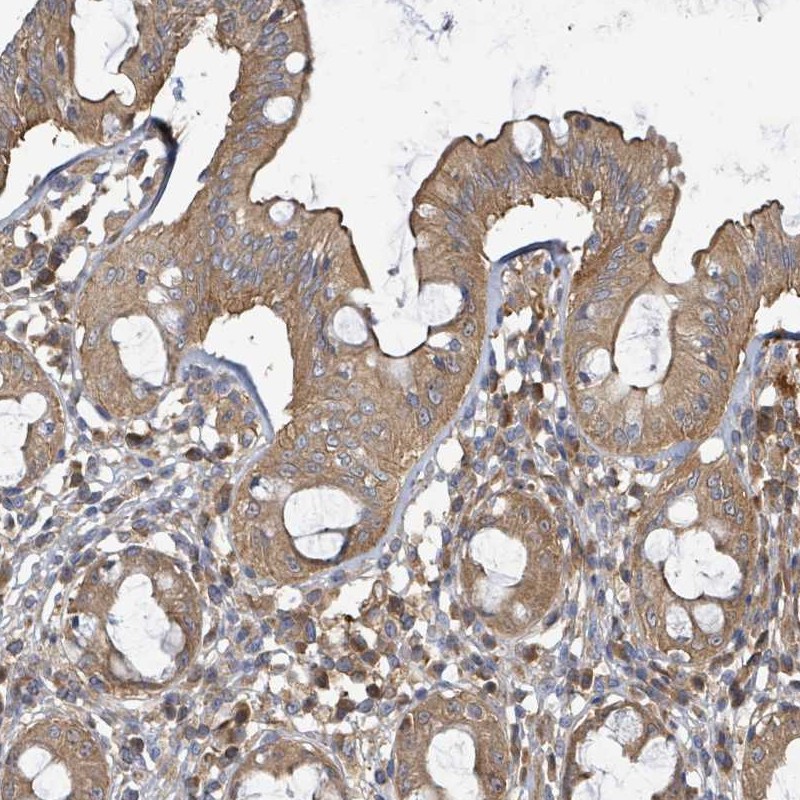

Immunohistochemical staining of human rectum shows moderate cytoplasmic and membranous positivity in glandular cells.